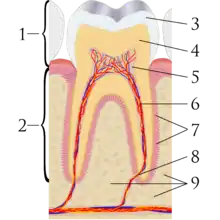

- Endodontics (also called endodontology) – Root canal therapy and study of diseases of the dental pulp and periapical tissues.